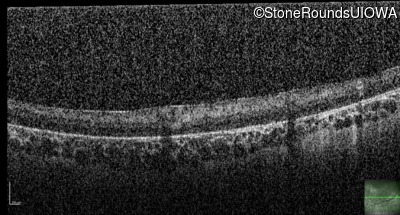

Optical Coherence Tomography - Right - No Light Perception

Exemplar / OCT Stack